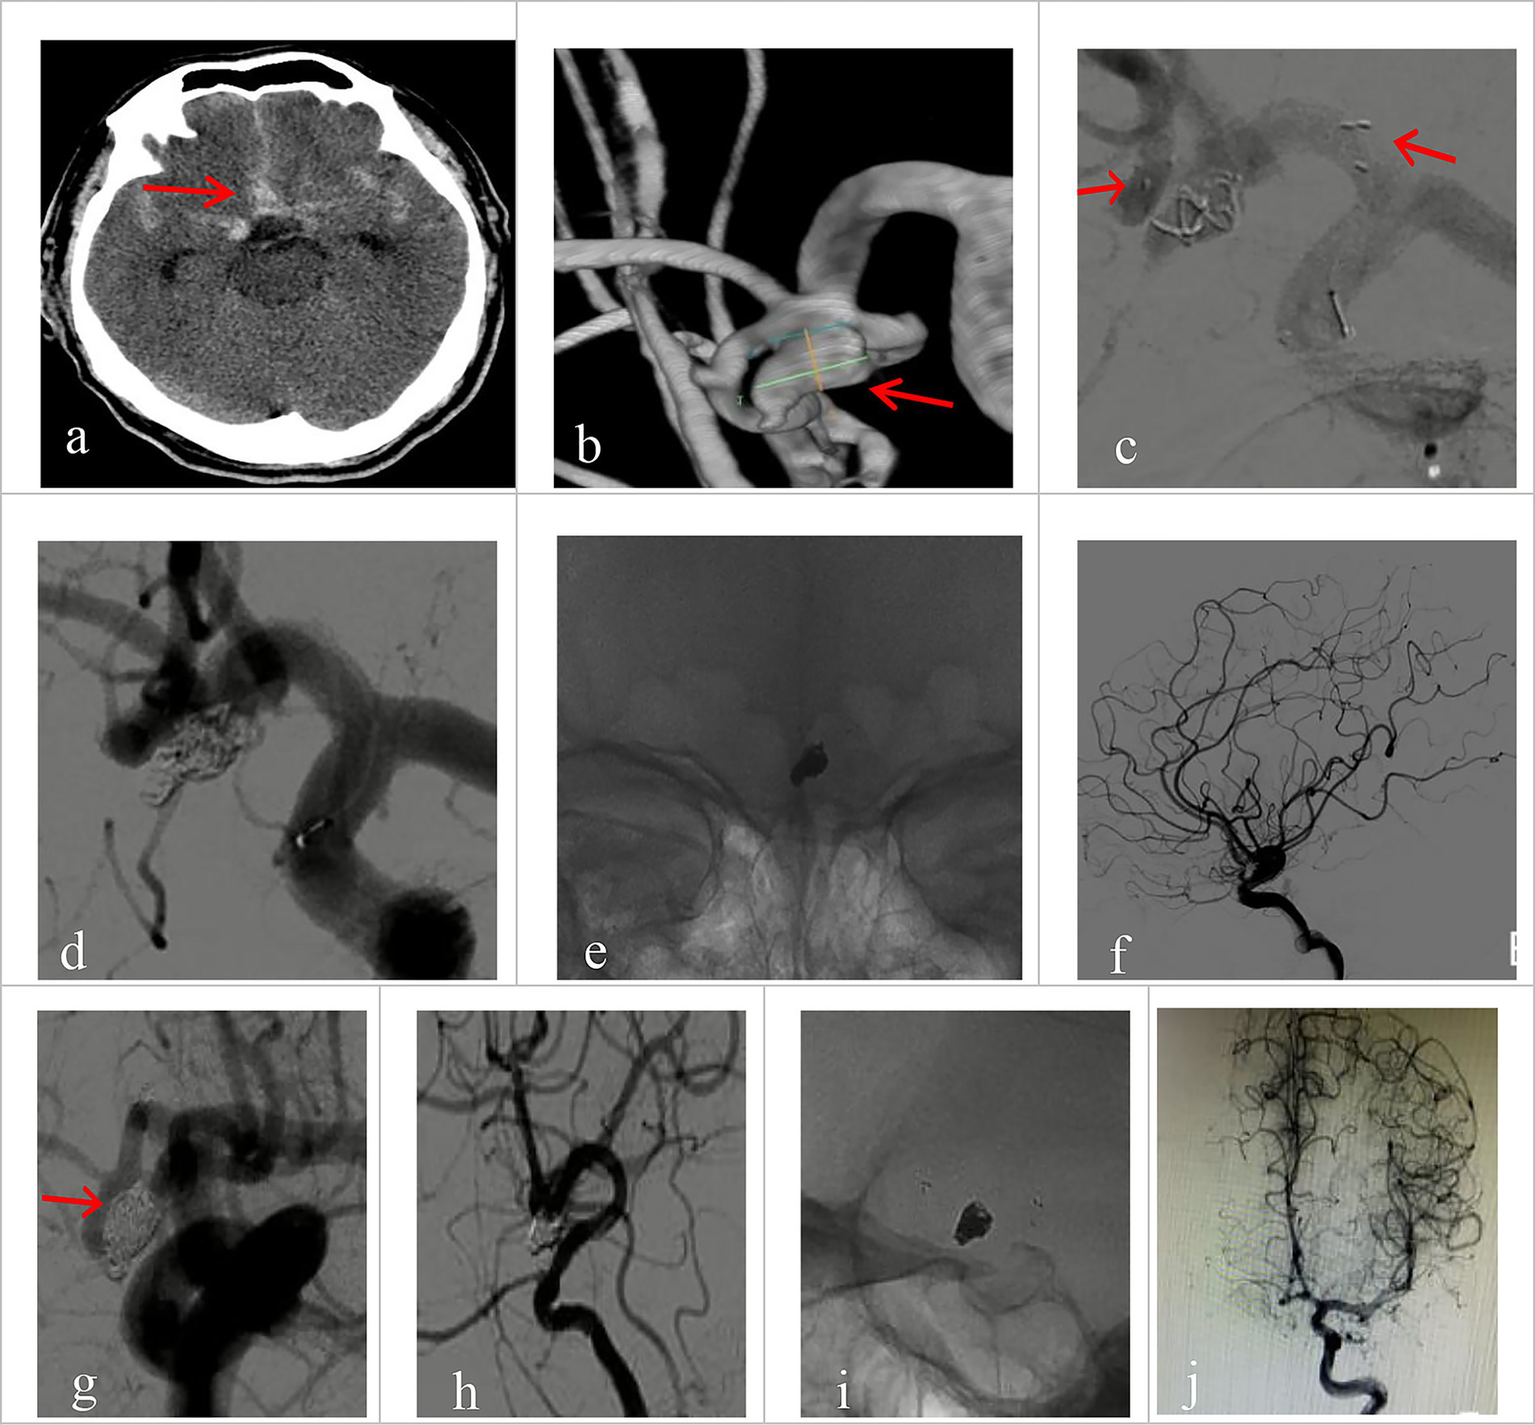

All 30 patients had effective Neuroform Atlas stent deployments, with good expansion and location. Twenty-three cases (76.7%) employed the double micro catheter approach, whereas 7 cases (23.3%) employed the single micro catheter technique. Immediate postprocedural angiography showed complete occlusion (RR Grade I) in 18 patients (94.7%) (Figure 1 shows the representative case), neck remnant (RR Grade II) in 0 (0%), and partial occlusion (RR Grade III) in 1 (5.3%). The data of the other 11 patients was unavailable because they refused to accept postprocedural angiography whose follow-up outcomes were good (mRS score ≤2). Clinical outcome was favorable in 29 patients (96.7%) and poor in 1 (3.3%). The mRS score was 3 in the single patient with poor clinical outcomes. Postprocedural angiographic and clinical outcomes are shown in Table 2 and Supplementary Figure 1. Procedure-related complications occurred in three patients (10%), including two cases of hemorrhagic complication and one case of thrombotic complication. No procedure-related death occurred. Contrast medium leakage was discovered during coil delivery in two patients with hemorrhagic complications, but it vanished during the angiography examination following rapid coil delivery. In terms of neurological recovery, mRS score was ≤2 (Figure 2 shows the representative case). One case was found post-procedural acute intrastent thrombosis. With slow injection of tirofiban hydrochloride (0.2 mL/kg) through the guiding catheter, angiography showed disappearance of thrombosis with effective reperfusion and neurological recovery, that was, mRS score ≤2. Postprocedural CT scan showed all patients had satisfactory embolization before smooth discharge from the hospital (Figure 3).

Figure 3. Imaging data of a 58-year-old male patient with a ruptured wide-necked anterior communicating artery (ACoA) aneurysm. (a) DSA angiography with 3D showed the location of a ruptured wide-neck ACoA aneurysm (red arrowhead). (b) The stent was successfully deployed from the ipsilateral A2 to the A1 segment. (c) The microcatheter was inserted into the aneurysm sac through the stent mesh to place the coils. Complete occlusion was achieved under final view (modified Raymond-Roy Class I) (red arrowhead). (d) Five hours postembolization developed right hemiparesis. Left ICA angiography showed cross flow to the M1 segment but with a filling defect in the right MCA area. There was thrombosis at the distal end of the stent (red arrowhead) and delayed development of the A2 segment of the left anterior cerebral artery with partial absence of distal branches and terminal vessels. (e,f) The microcatheter was delivered into in-stent thrombosis to give an infusion of tirofiban (0.2 mL/kg) (red arrowhead). (g) DSA showed that the A2 segment of the left anterior cerebral artery was completely reperfusion, and thrombus was greatly reduced.